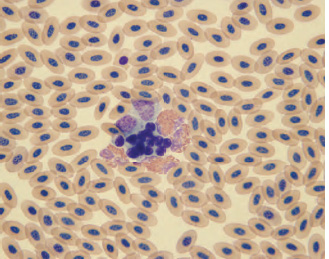

Variations in erythrocyte color include polychromasia and hypochromasia. Polychromatophilic erythrocytes occur in low numbers (usually less than 5% of the total erythrocyte count) in the peripheral blood of most normal birds. Polychromatophilic erythrocytes are similar in size to mature erythrocytes and appear as reticulocytes when stained with vital stains, such as new methylene blue. The cytoplasm appears weakly basophilic, and the nucleus is less condensed than the nucleus of mature erythrocytes (See Fig. 1.13). The degree of polychromasia can be graded according to the guideline in Table 1.1.

Hypochromatic erythrocytes are abnormally pale in color when compared to normal mature erythrocytes and have an area of cytoplasmic pallor that is greater than one-half the cytoplasmic volume (See Fig. 1.14). They may also contain cytoplasmic vacuoles and round pyknotic nuclei. A significant hypochromasia will be reflected as a decrease in the MCHC. The degree of hypochromasia can be estimated using the scale in Table 1.1.

Fig. 1.13. The polychromatic avian erythrocytes (arrows) are represented by a light blue cytoplasm. (Wright’s stain, 1000×)

Reticulocytes are the penultimate cell in the erythrocyte maturation series and their presence in the peripheral blood of normal birds suggests that final stages of red cell maturation occur in circulating blood. Determination of reticulocyte concentration can be made by staining erythrocytes with a vital stain, such as new methylene blue. Reticulocytes have a distinct ring of aggregated reticular material that encircles the nucleus (See Fig. 1.15). As the cells mature, the amount of aggregated reticular material decreases and becomes more dispersed throughout the cytoplasm. With further maturation, the reticular material becomes nonaggregated and the cells begin to resemble the “punctate” reticulocytes of felids. Most mature avian erythrocytes contain a varying amount of aggregate or punctate reticulum. Reticulocytes that reflect a current erythrocyte regenerative response are those that have a distinct ring of aggregated reticulum that encircles the red cell nucleus (Campbell, 1995; Hawkey and Dennett, 1989). Significantly high numbers of these cells would represent a regenerative response to anemia.

Fig. 1.14